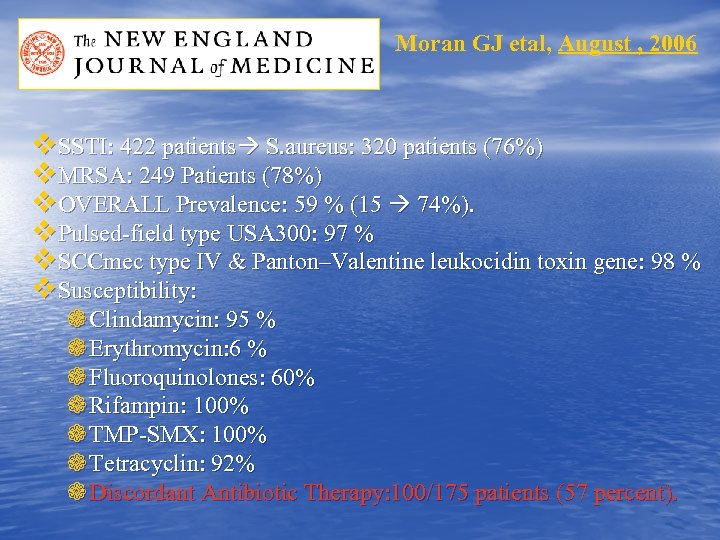

Moran GJ etal, August , 2006 v SSTI: 422 patients S. aureus: 320 patients (76%) v MRSA: 249 Patients (78%) v OVERALL Prevalence: 59 % (15 74%). v Pulsed-field type USA 300: 97 % v SCCmec type IV & Panton–Valentine leukocidin toxin gene: 98 % v Susceptibility: ❁ Clindamycin: 95 % ❁ Erythromycin: 6 % ❁ Fluoroquinolones: 60% ❁ Rifampin: 100% ❁ TMP-SMX: 100% ❁ Tetracyclin: 92% ❁ Discordant Antibiotic Therapy: 100/175 patients (57 percent).

Moran GJ etal, August , 2006 v SSTI: 422 patients S. aureus: 320 patients (76%) v MRSA: 249 Patients (78%) v OVERALL Prevalence: 59 % (15 74%). v Pulsed-field type USA 300: 97 % v SCCmec type IV & Panton–Valentine leukocidin toxin gene: 98 % v Susceptibility: ❁ Clindamycin: 95 % ❁ Erythromycin: 6 % ❁ Fluoroquinolones: 60% ❁ Rifampin: 100% ❁ TMP-SMX: 100% ❁ Tetracyclin: 92% ❁ Discordant Antibiotic Therapy: 100/175 patients (57 percent).